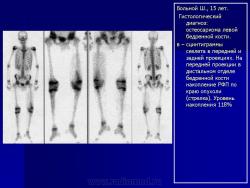

Для уточнения диагноза, локализации опухоли, выявления дополнительных очагов заболевания, определения ее отношения к окружающим тканям и контроля за эффективностью проводимой химиотерапии возможно проведение дополнительных исследований: компьютерная томография, магнито-резонансная томография, ангиография, остеосцинтиграфия, УЗИ.